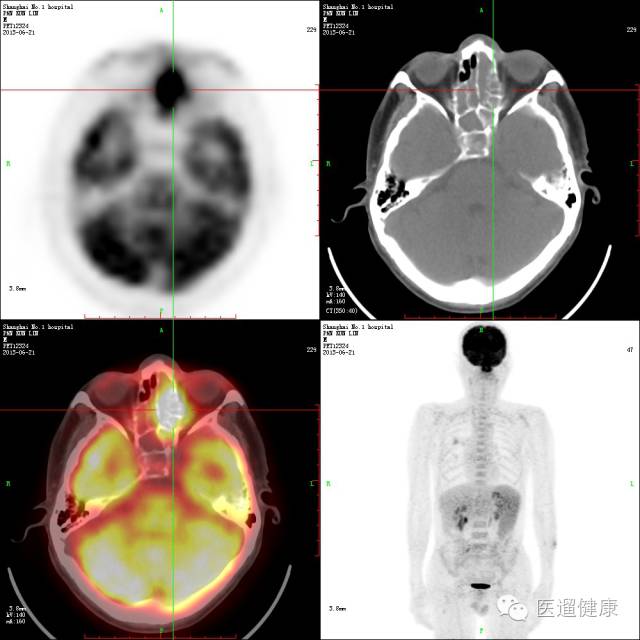

呼吸科病例

病患:男,58岁。反复咳嗽咳痰10年,发热3周,入住呼吸科。

胸部CT:肺气肿,右肺上叶后段慢性炎症,

支气管镜:未见新生物,各管腔可见少量脓痰,以左肺上叶及右下叶背段为多。下一步怎么办?

↑

→

通过检查诊断出病患右肺上叶后段小斑片实变影,放射性轻度增高,SUV最大值约2.3。

鼻咽顶后壁、左鼻腔及右鼻腔鼻中隔处软组织增厚,左中、上鼻道软组织影填塞,左额窦、双筛窦、蝶窦、左上颌窦内软组织密度影填塞,SUV最大值约12.8。

脾脏增大,放射性普遍轻度增高,SUV最大值约2.8

该病例PET/CT影像诊断:

淋巴瘤病灶可能性大,建议活检协诊。

鼻咽部活检病理回报:(鼻腔新生物)大量坏死及少量粘膜,粘膜内异型的淋巴细胞浸润,瘤细胞表达:LCA(+),CD56(+),Vim(+),CD3(弱+),CD20(-),CD79α(-),CK(-),Ki67(60%+),

疑为NK/T细胞淋巴瘤,鼻型。